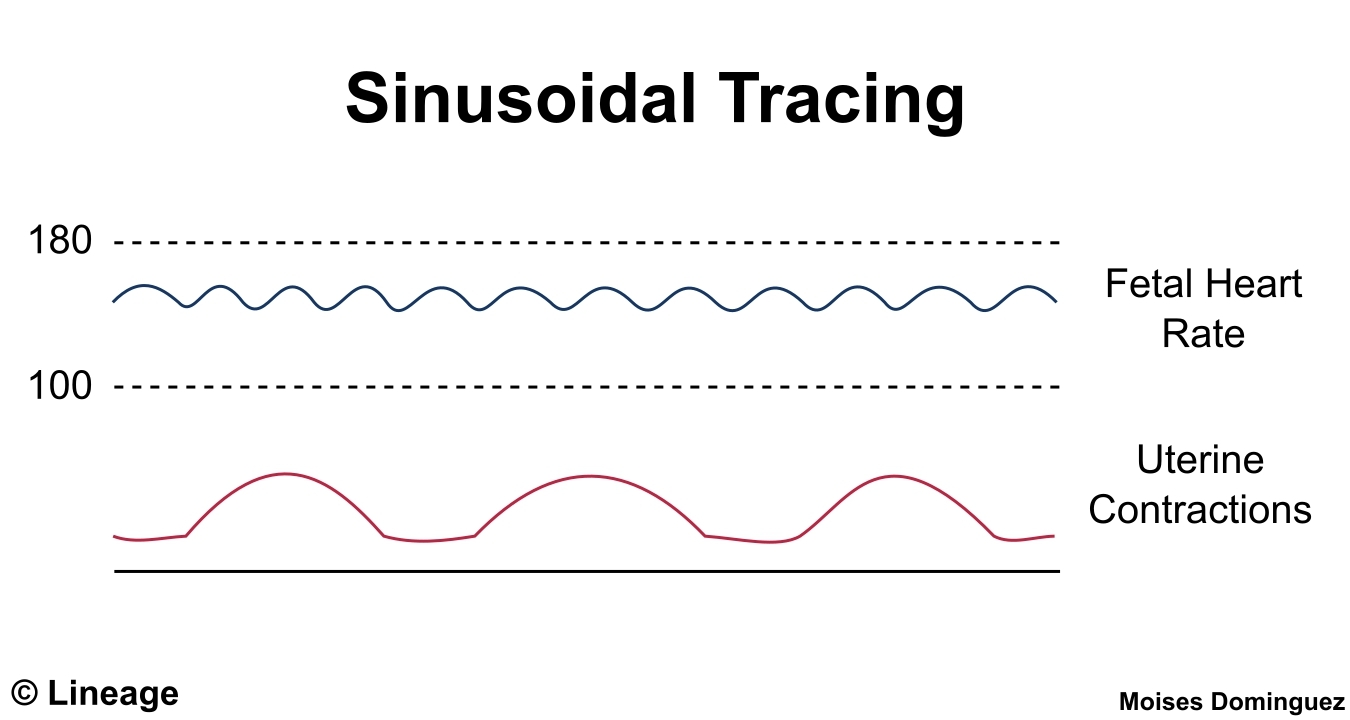

These patterns are characterized by a smooth, regular, and symmetrical waveform on the fetal heart rate monitor. They are different from the typical heart rate patterns seen during labor and delivery and may indicate certain underlying conditions.

Sinusoidal fetal heart rate patterns can be a cause for concern as they may be associated with fetal distress. It is important for healthcare providers to monitor these patterns closely and take appropriate action to ensure the well-being of both the mother and the baby.

Intrapartum Fetal Assessment Obstetrics Medbullets Step 2 3

PDF Title Sinusoidal Heart Rate Pattern Reappraisal Of Its Definition And Clinical Significance Semantic Scholar

Figure 2 From Title Sinusoidal Heart Rate Pattern Reappraisal Of Its Definition And Clinical Significance Semantic Scholar